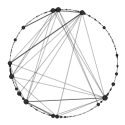

The pathways specific to early PD show a great involvement of the immune system, which is greatly stimulated by inflammation especially located in particular brain regions (mainly substantia nigra). Indeed, we identified: GO:0006952 i.e. defense response, GO:0045087 i.e. innate immuno response also visualized in Figure 3, GO:0006955 i.e. immune response and GO:0030097 i.e. hemopoiesis.

|

|

| (a) early PD patients | (b) controls |

From Figure 3 it is clear that since the early stages of PD the innate immune system is severly compromised: the body is highly subjected to the invasion and proliferation of microbes (like bacteria or viruses), resulting in a debilitated organism, less effective in fighting the consequent inflammation.